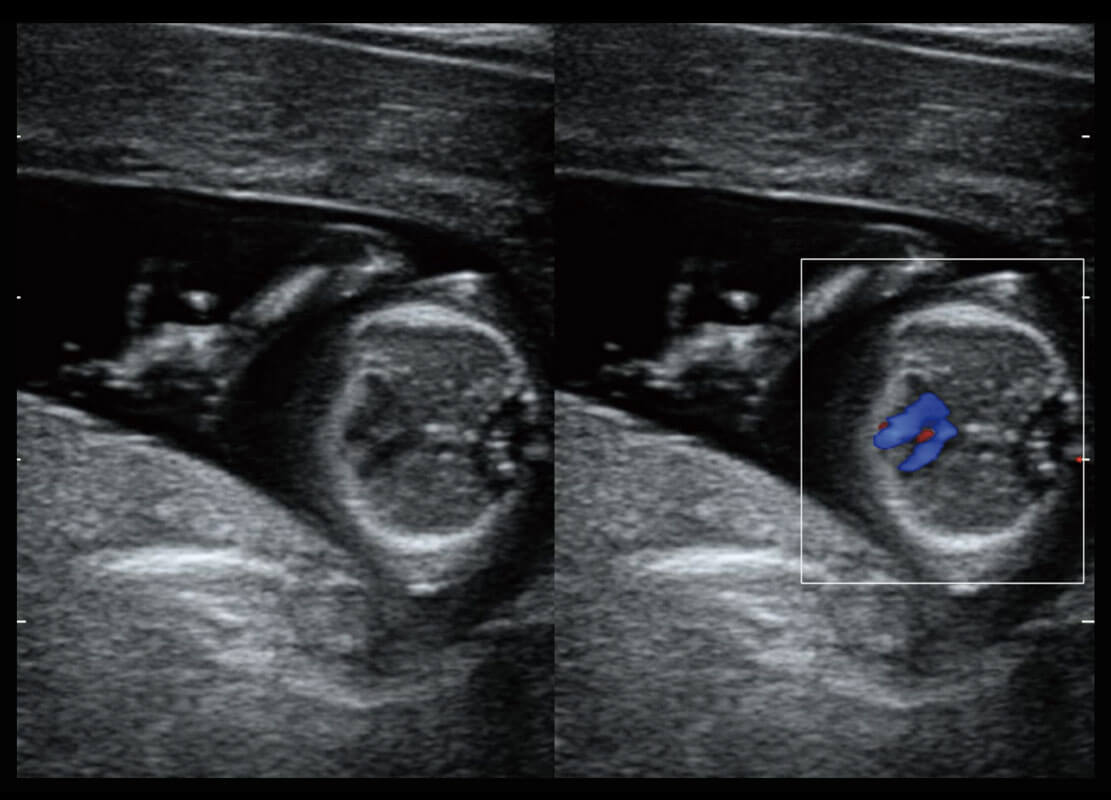

S-Fetus能够助您在实时扫查过程中自动识别标准切面、自动测量并录入报告。一个按键,即可快速、高效地获取胎儿生理指标,简化您的产科检查操作。

1 OFD(HC): 87.03 mm

HC: 251.00 mm

GA: 27w 1d

HC/AC: 96.13 %

2 BPD: 70.56 mm

GA: 28 w 2d

S-Fetus(acq.)

&

S-Fetus(meas.)